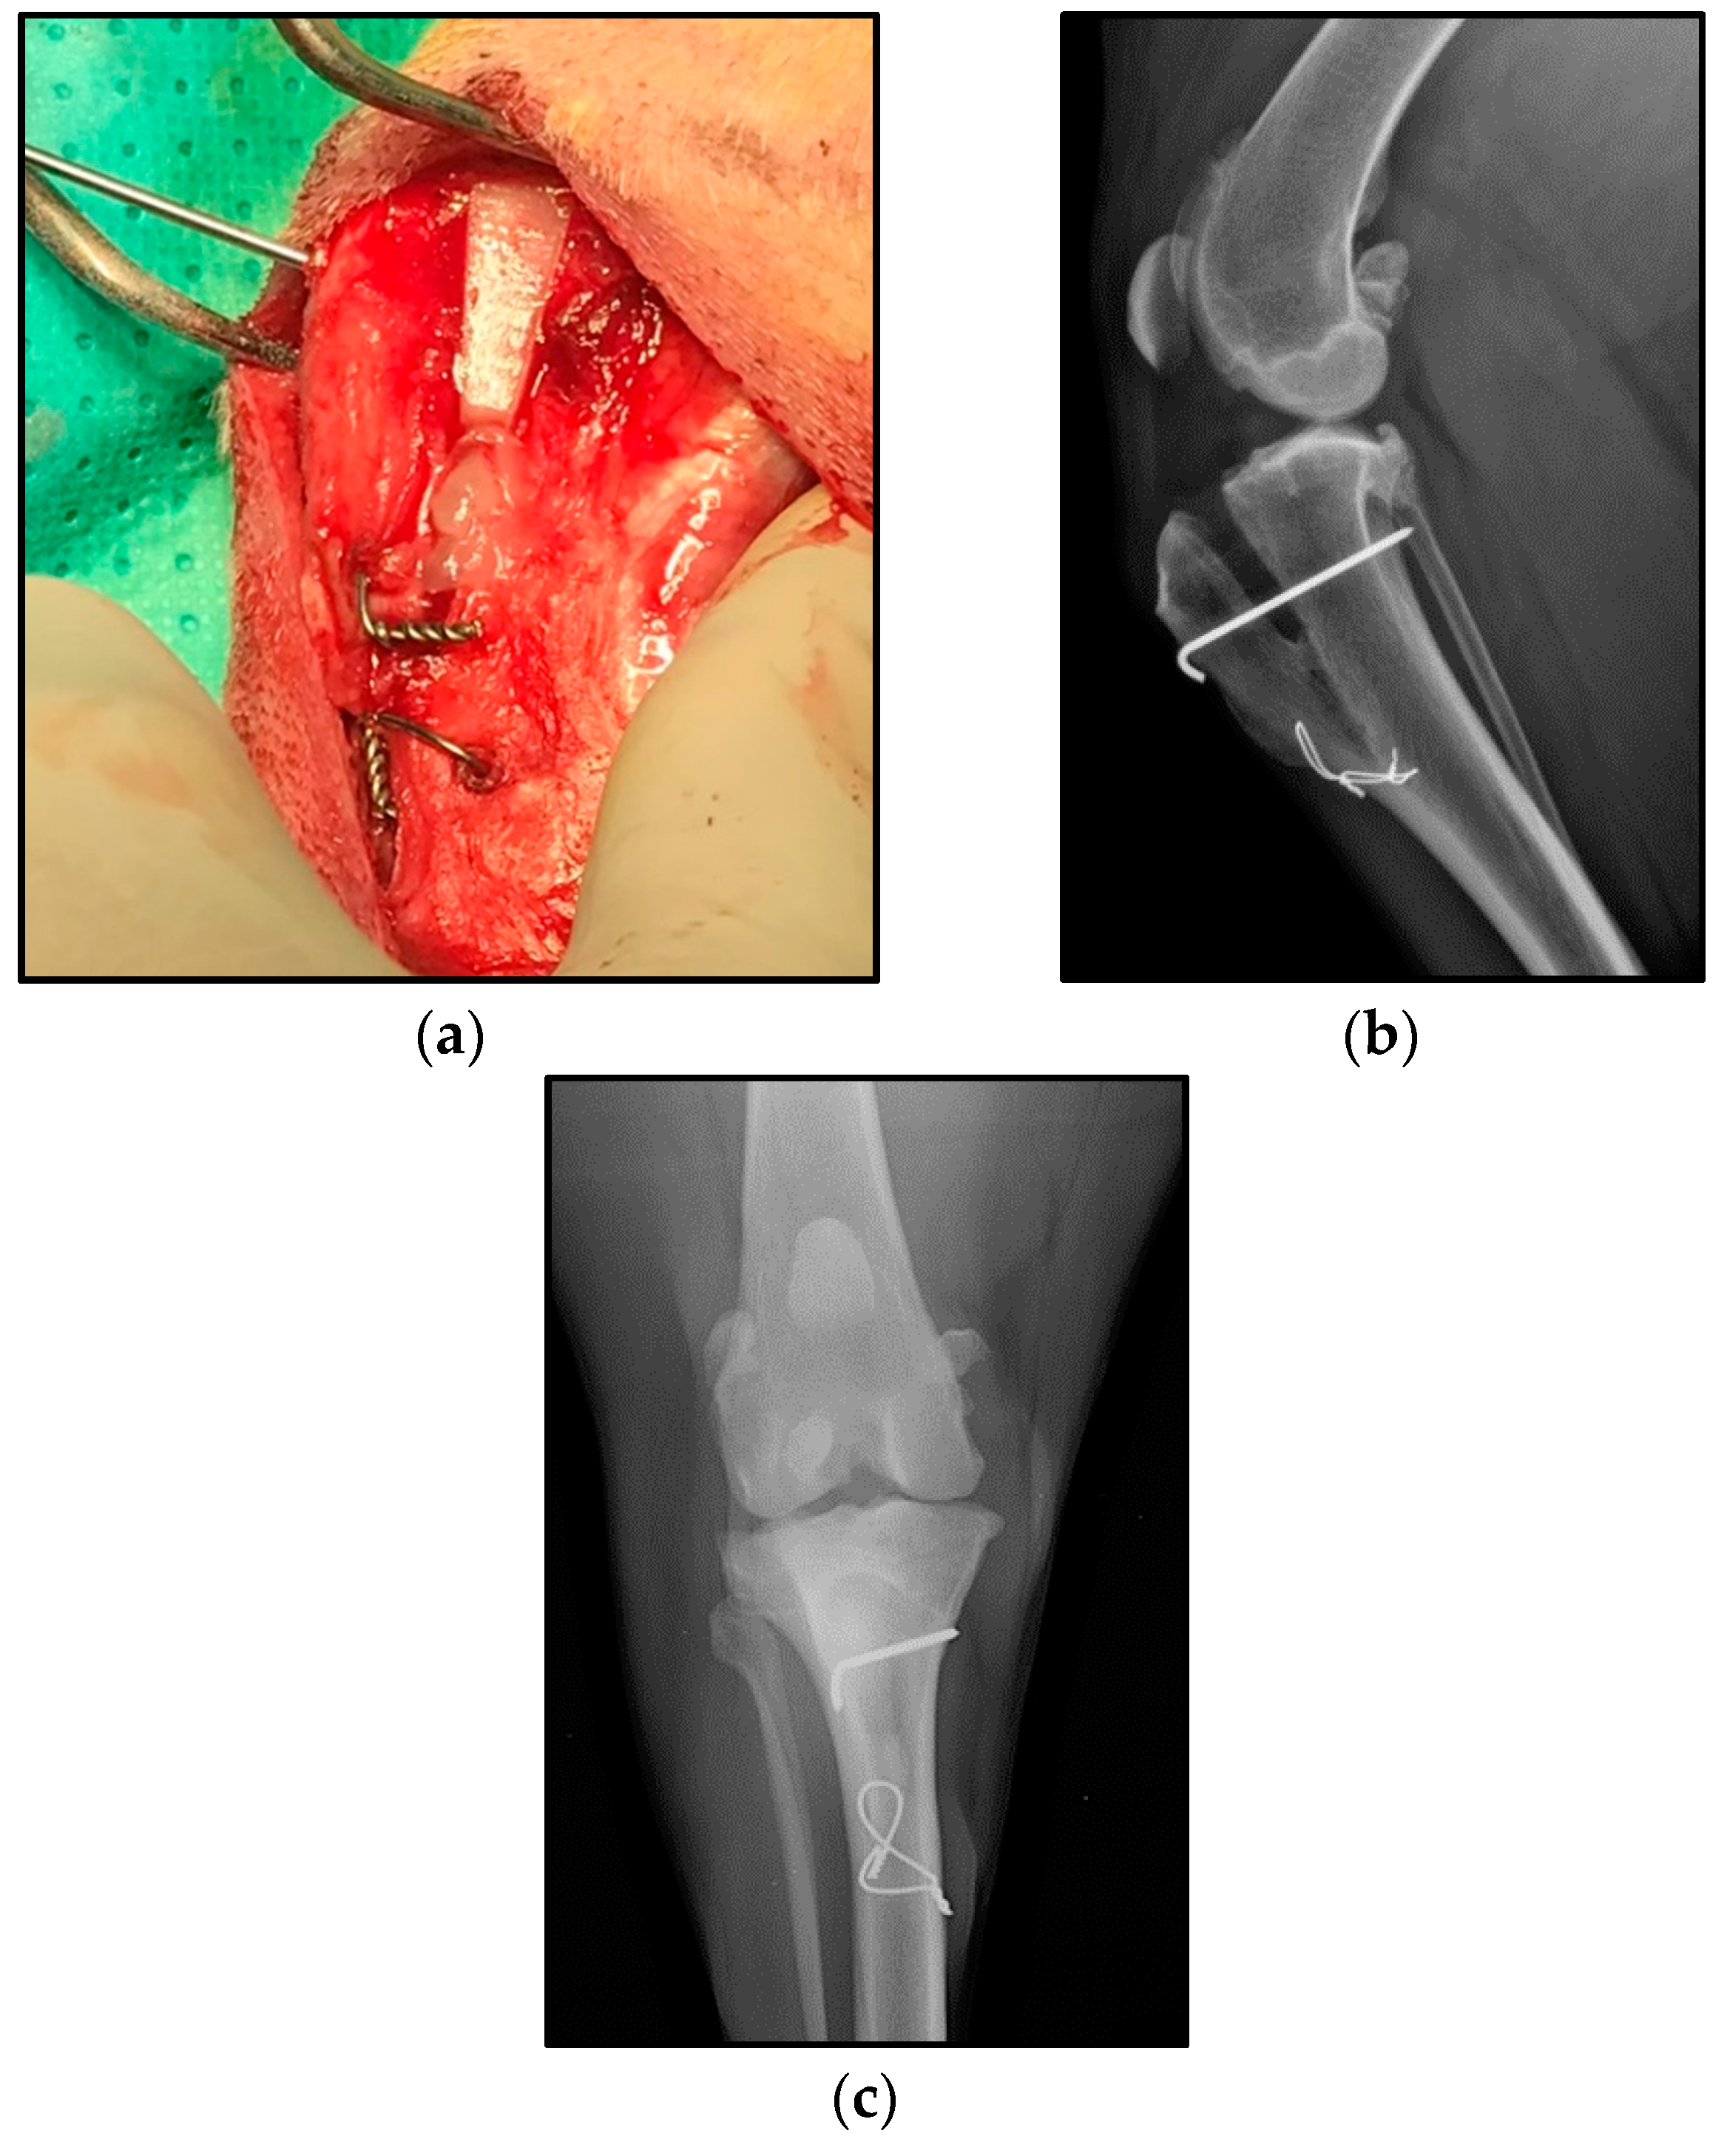

2. Materials and Methods

2.1. Clinical Trial

2.2. PRGF Fabrication

2.4. Radiographic Assessment

- Valiño-Cultelli, V.; Varela-López, Ó.; González-Cantalapiedra, A. Preliminary Clinical and Radiographic Evaluation of a Novel Resorbable Implant of Polylactic Acid (PLA) for Tibial Tuberosity Advancement (TTA) by Modified Maquet Technique (MMT). Animals 2021, 11, 1271. [Google Scholar] [CrossRef]